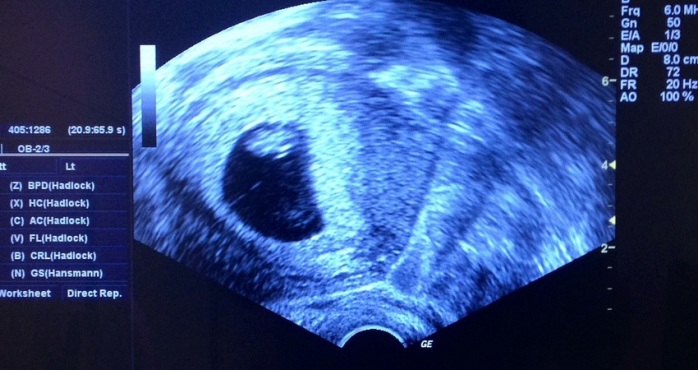

Como detalla la revista femenina Cosmopolitan, el experto a cargo de su examen descubrió que tenía órganos femeninos funcionando perfectamente. Esta condición se llama Síndrome del conducto Müllerian persistente (PMDS) y afecta a los hombres, quienes además de los genitales masculinos, poseen un útero y a veces, trompas de falopio.

En el caso de “Rob” (nombre clave para ocultar su identidad), este posee un útero funcional, ovarios y cervix. “El diagnóstico cayó como una bomba. Nunca me vi a mí mismo como algo más que una persona común que tiene una vida sexual normal. Ahora parece que podría quedar embarazado”, detalló el afectado.